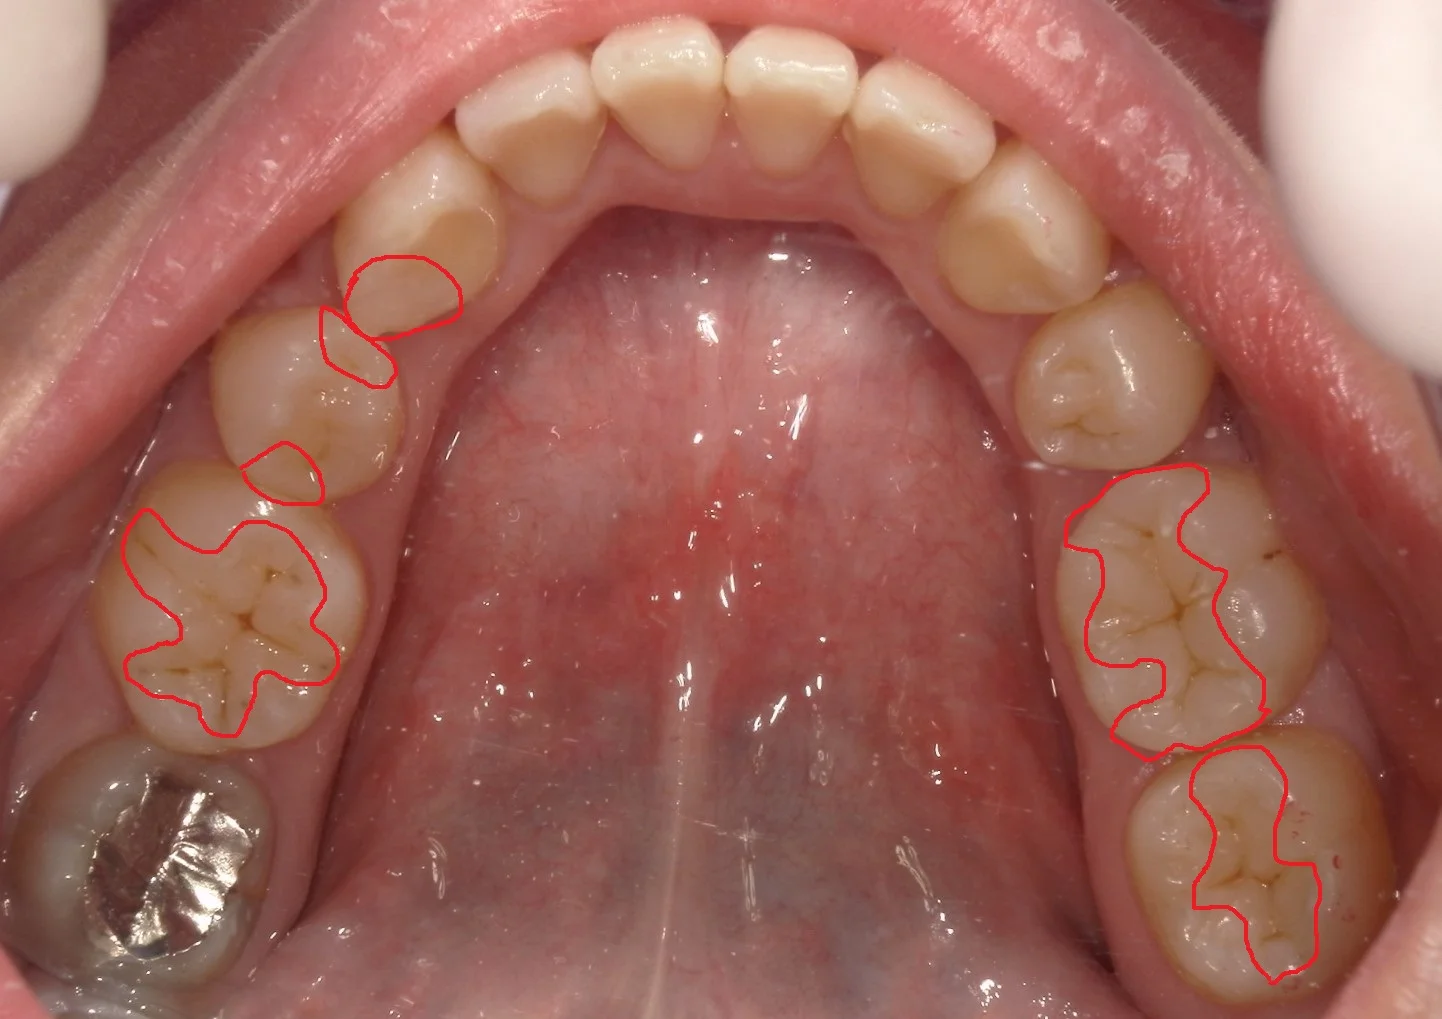

正解はこんな感じですヽ(゚∀゚)ノ パッ☆

計4回で治療終了まで行きました!

もちろんいつかはダメになってしまいますが、なるべく長持ちさせていただきたいと思います!